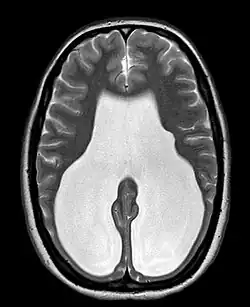

Colpocephaly is characterized by disproportionately large occipital horns of the lateral ventricles (also frontal and temporal ventricles in some cases). MRI and CT scans of patients demonstrate abnormally thick gray matter with thin poorly myelinated white matter. This happens as a result of partial or complete absence of the corpus callosum. Corpus callosum is the band of white matter connecting the two cerebral hemispheres. The corpus callosum plays an extremely important role in interhemispheric communication, thus lack of or absence of these neural fibers results in a number of disabilities.[12]

The lemon sign on CT scans of patients refers to the shape of the fetal skull when the frontal bones lose their normal convex contour and appear flattened or inwardly scalloped. This gives the skull a shape similar to that of a lemon. The sign is seen on transverse sonograms of the fetal cranium obtained at the level of the ventricles. A special case is found in literature where lissencephaly, colpocephaly, and septal agenesis are all present together. The CT scans of the patient shows the ventricular system having a unique appearance of a crown of a king. This is referred to as the 'CROWN SIGN'.[8]

After birth, MR imaging can be done to look for cephalic abnormalities. This is the most commonly used method for diagnosing colpocephaly. Physicians look for abnormally large occipital horns of the lateral ventricles and diminished thickness of white matter.[12] Spinal tapping is not a preferred method for diagnosis because newborn babies with colpocephaly or hydrocephaly have open fontanelles which makes it difficult to collect CSF. Also, colpocephaly is not associated with increased pressure.[13]